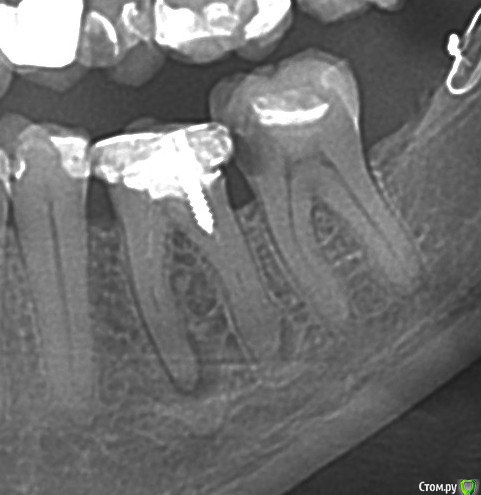

igorstom Опубликовано 10 декабря, 2016 Автор Поделиться Опубликовано 10 декабря, 2016 2014 год. Ну ведь явная же гранулема (кисто-гранулема)? Зуб 3.6 Ссылка на комментарий

igorstom Опубликовано 10 декабря, 2016 Автор Поделиться Опубликовано 10 декабря, 2016 В 2014 году у пациента были жалобы по поводу припухлости в области 3.6 зуба (делали периостотомию и назначили антибиотики - в поликлинике, и также настойчиво предлагали удалить), болезненность при накусывании в этот период. Попробовал всё перелечить. Ссылка на комментарий